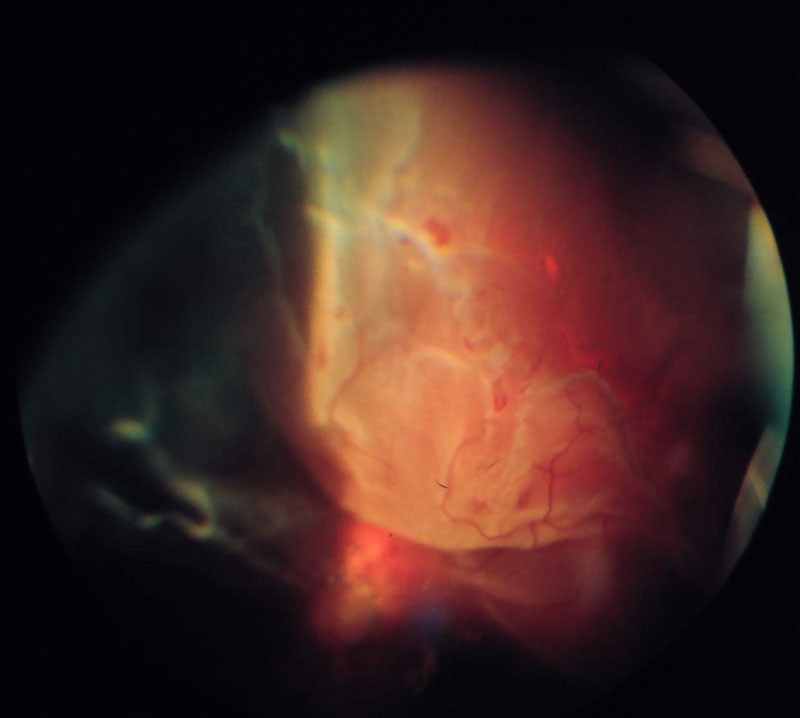

30. ábra

30. ábra Proliferativ diabeteses retinopathia, részleges hátsó üvegtesti leválás következtében fellépett masszív, retrohyaloideális vérzés képe. Az üvegtest elülső részei tiszták, a vérzés haematomaszerű jellege, a hátsó üvegtesti kéreg, a papilláról az üvegtesti térbe nyúló proliferativ membrán körvonalai jól kivehetőek.